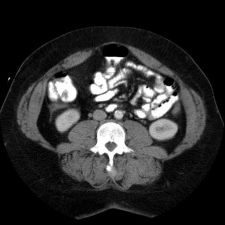

This is an image from a contrast enhanced abdominal CT.

contrast enhanced abdominal CTZoom (34KB)

This image shows what finding? What might it indicate?

Fluid in the right paracolic gutter, and a thickened, inflamed appendix with thickening of the adjacent cecal wall.

Differential: Acute appendicitis is by far the most likely diagnosis.

No appendicolith is seen in this case.

The appendix is normally less than 7 mm in diameter, or if fluid filled, the wall can be up to 3mm thick. This appendix is distended, and the adjacent stranding and fluid indicates the inflammatory process which is causing peritoneal irritation and pain. Here is a series of images showing a normal appendix using similar technique. Note the thin walls of the normal appendix.